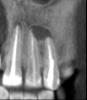

При прохождении КТ в 2011 г .была выявлена киста в области 21-21 зуба.

В 2003 году была проведена операция по резекции верхушки корней данных зубов, в 2008 году каналы зубов были заново перелечены и усилены металлическими штифтами. При наращивании коронковой части зубов 21-22 терапевт удлинил зубы вследствие чего на них увеличилась нагрузка и доставила дискомфорт.

post-23088-0-05077900-1320069184_thumb.jpg

post-23088-0-85945100-1320069186_thumb.jpg

post-23088-0-44942700-1320069187_thumb.jpg

post-23088-0-08601700-1320069188_thumb.jpg

post-23088-0-77081900-1320069268_thumb.jpg